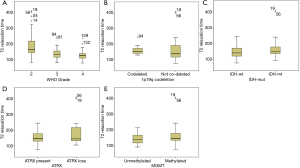

Table 3 and Figure 3 show the median T2 relaxation times and comparisons between molecular categories. The T2 relaxation time distribution was significantly different between IDH-mt and IDH-wt gliomas (P=0.001) and between MGMT-methylated and MGMT-unmethylated gliomas (P=0.03). Borderline significance was found between 1p/19q-codeleted and not co-deleted gliomas (P=0.05). No distribution difference was observed between ATRX gene loss and present gliomas; however, when T2 relaxation times were used as a diagnostic tool to predict molecular category, they could not make accurate predictions, with all AUCs were between 0.5–0.7. Table 4 shows the ROC analysis for predicting the IDH status, with an AUC of 0.687.